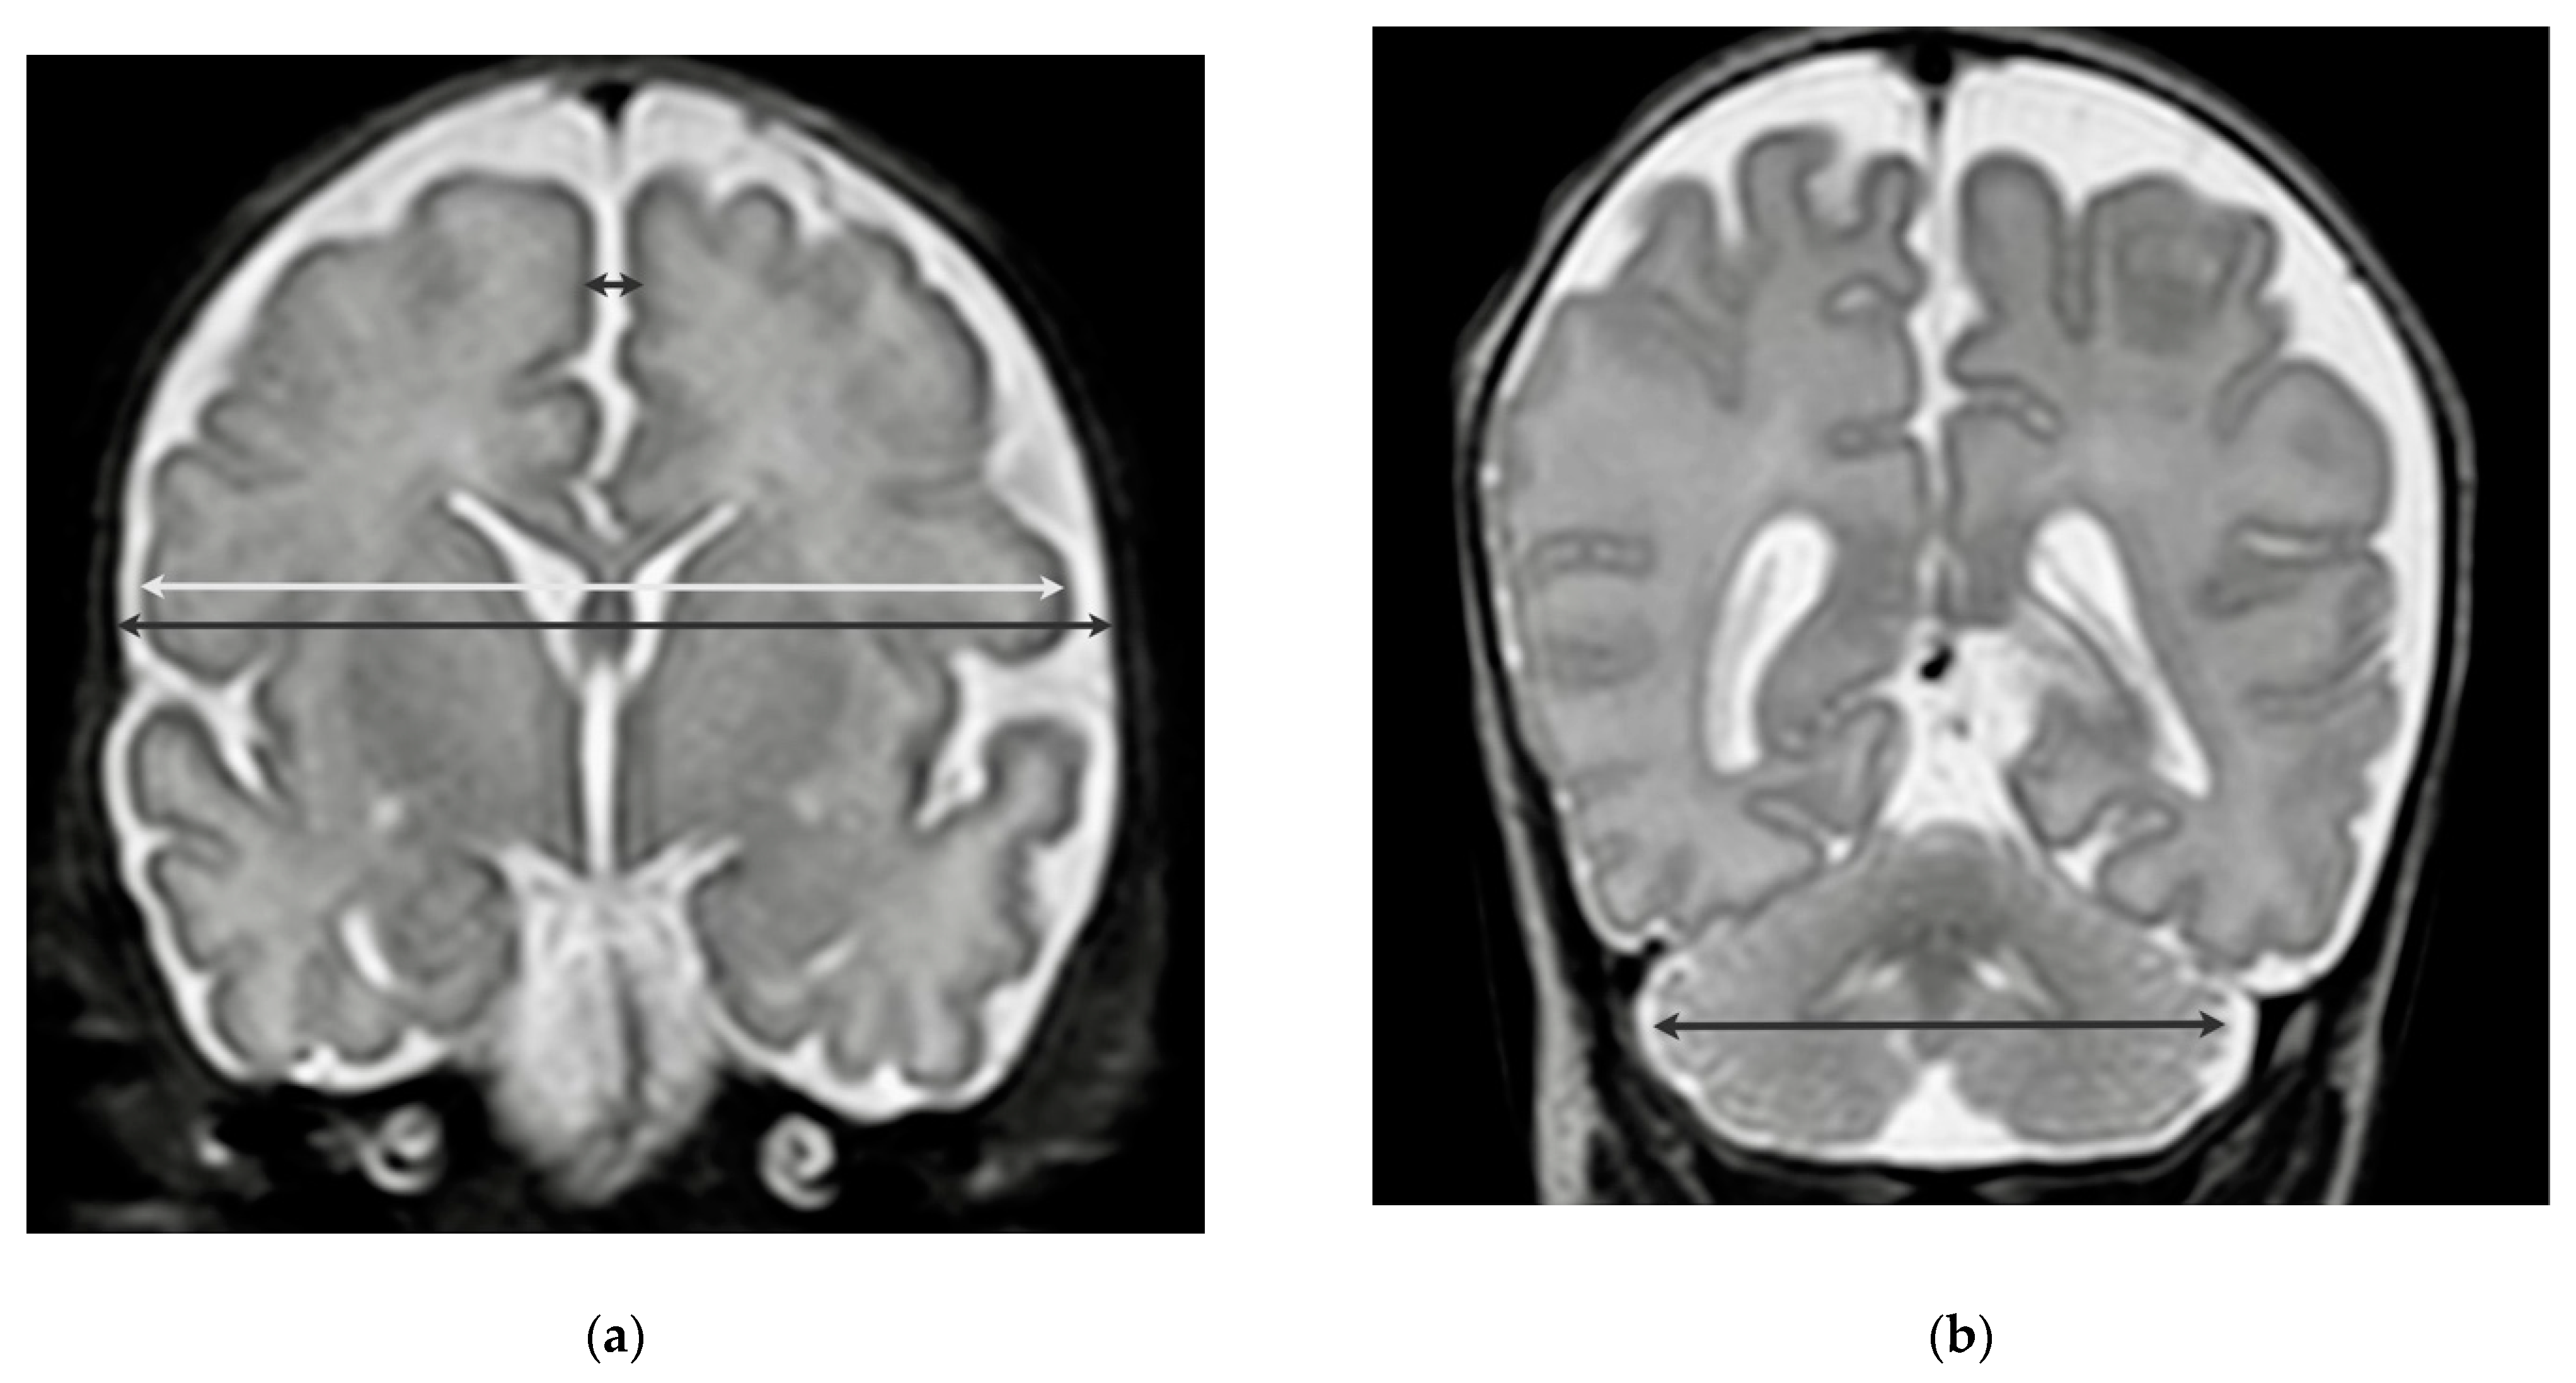

2.2. Neuroimaging

| cBPD, mm | 71.1 (68.9, 74.1) |

| bBPD, mm | 76.2 (73.7, 79.5) |

| IHD, mm | 2.5 (2.0, 3.0) |

| tCD, mm | 47.6 (45.7, 49.4) |

| cBPD, Z-Score | −2.3 (−2.8, −1.8) |

| bBPD, Z-Score | −2.2 (−2.9, −1.7) |

| IHD, Z-Score | 0,3 (−0.3, 0.8) |

| tCD, Z-Score | −0.7 (−2.1, 0.0) |